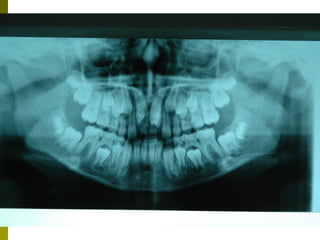

Πρώτη σχολική ηλικία 6-10 ετών

   Αρχίζει αλλαγή των τομέων και η ανατολή των

πρώτων μόνιμων γομφίων (μεικτή οδοντοφυΐα)

   Παρατηρούμε η αλλαγή δοντιών να γίνεται με τη

σωστή σειρά και στη σωστή θέση

   Μπορεί να χρειαστεί πρώιμη ορθοδοντική

θεραπεία, για να αποφευχθούν πιο δύσκολες και

πολύπλοκες εργασίες αργότερα

   Διατήρηση νεογιλών δοντιών στον οδοντικό

φραγμό μέχρι τη φυσιολογική τους απόπτωση